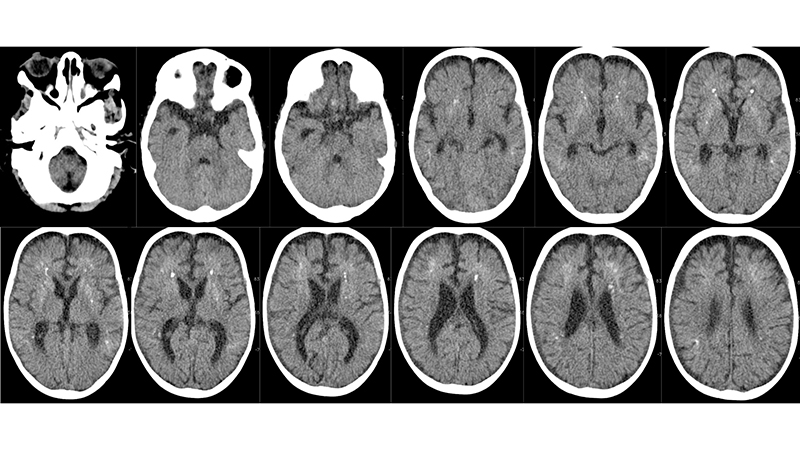

- Στην αξονική τομογραφία πρό μηνός, βλέπουμε υποφλοιώδεις και υποεπενδυματικές μικροαποτιτανώσεις αποτέλεσμα μικροϊσχαιμικών αλλοιώσεων εξαιτίας της φλεβικής υπερτάσεως. Συνυπάρχει αρχόμενη διάταση των κοιλιών.

- Στην αξονική τομογραφία εισαγωγής του, μετά σκιαγραφικό βλέπουμε επέκταση των μικροϊσχαιμικών αλλοιώσεων στο εγκεφαλικό στέλεχος με πρόσληψη σκιαγραφικού,

- ενώ φαίνονται και αμφοτερόπλευρα υποσκληρίδια αιματώματα στην κυρτότητα των ημισφαιρίων, κυρίως δεξιά,

- παρομοίως υποφλοιώδεις και υποεπενδυματικές μικροαποτιτανώσεις υπερσκηνιδιακά και υποσκληρίδια αιματώματα.